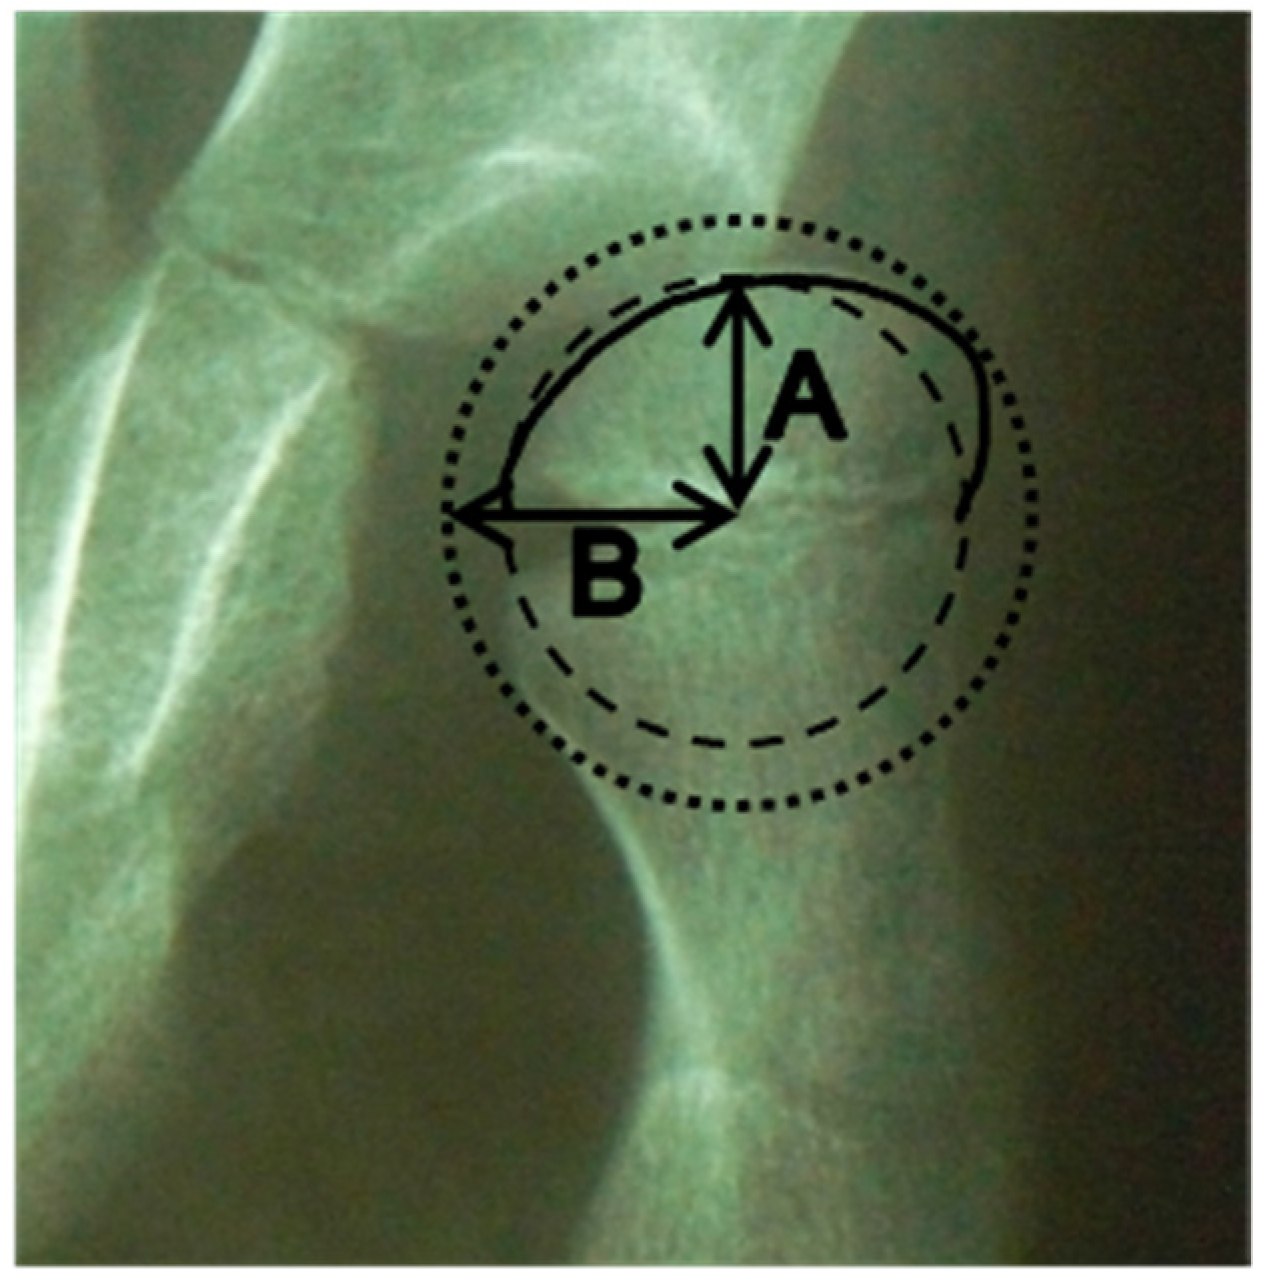

The femoral head deformity (FHD) was classified from grade A to D, according to visual inspection of the femoral head shape on the anteroposterior radiograph [14]. A collapsed femoral head could not be classified using the femoral head deformity grade classification and was considered to be avascular necrosis (AVN). The femoral head sphericity was measured using a previously described modified Mose technique [15], with ratios closer to 1 indicating a more spherical head [Figure 1].

Figure 1. Measurement technique of the femoral head sphericity. A indicates the radius of the smallest circle that fits within the contour of the femoral head. B indicates the radius of the largest circle which encloses the femoral head. The ratio is calculated by A divided by B.